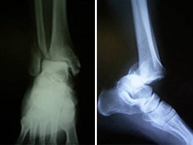

La articulación del tobillo une la pierna con el pie y su funcionamiento permitela normal deambulación que realizamos. Están implicados los tercios inferiores de la tibia y el peroné que articulan con el astrágalo del pie. Es una región anatómica muy susceptible de recibir lesiones fundamentalmente de dos tipos; alta energía en accidentes laborales o de tráfico produciendo las temibles fracturas de pilón tibial o de baja energía en el ámbito deportivo por mecanismos de torsión produciendo las fracturas maleolares. Las fracturas de pilón tibial se acompañan de gran afectación de los tejidos circundantes al hueso por lo que requieren un tratamiento muy meticuloso de estos tejidos antes de resolver la lesión ósea. En las fracturas maleolares, características de deportes de salto y giro como fútbol, basket, monopatín, volley, artes marciales, etc., la lesión se produce a nivel del mecanismo de pinza conocido como mortaja tibioastragalina que impide en condiciones normales que el pie se separe de la pierna.

Las lesiones del tobillo, como en general de todas las articulaciones del esqueleto, requiere una reconstrucción anatómica para evitar la rigidez articular por lo que se realizará una cirugía rápida y mínimamente invasiva para reincorporar al paciente lo antes posible a su actividad previa.